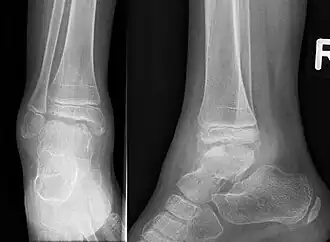

M. Trevor tritt einseitig zumeist an der unteren Extremität auf und führt im Laufe des Wachstums zur Fehlstellung und Deformierung des Gelenkes. Assoziation mit Enchondromatose ist beschrieben[3]. Der schmerzlose Überwuchs fällt im Kleinkindesalter auf, häufig an den Fußknochen, am Kniegelenk oder Sprunggelenk.

Die Diagnose kann im Röntgenbild gestellt werden aufgrund der typischen Lokalisation, des unregelmäßigen Überwuchses und des Auftretens von mehreren nicht miteinander verbundenen Knochenkernen, die an Epiphysen angelagert sind.[4] Eine Diagnosesicherung ist im MRT möglich.